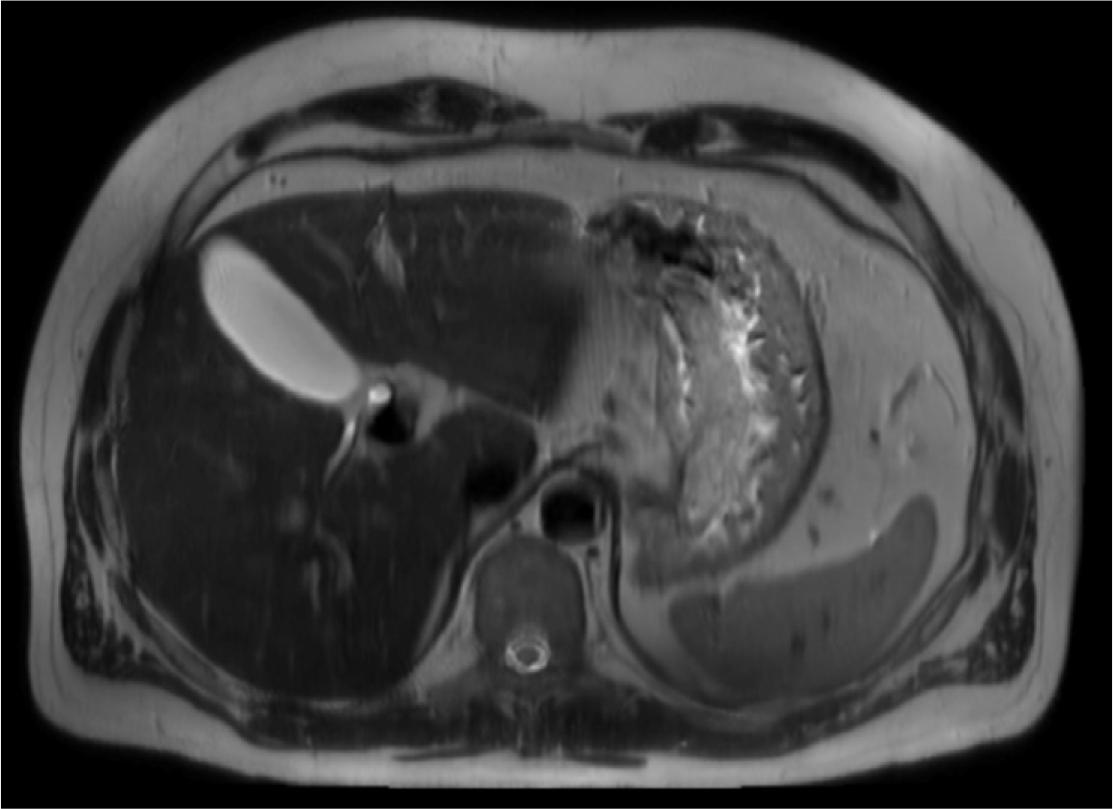

Figure 1.

![Axial fused [68Ga]Ga-DOTA-TATE PET/CT image at the level of the upper abdomen. Moderately increased radiotracer uptake is visible along the lesser curvature of the stomach near the cardiac orifice. This area corresponds to the gastric wall thickening visualized previously in the MRI, where a 106 × 34 mm lesion was seen. Although the uptake is not significantly intense, its location aligns with the previously identified abnormality. At the time of the MRI, differential diagnoses included gastric lymphoma, hypertrophic gastritis, and Zollinger-Ellison syndrome.](https://sciendo-parsed.s3.eu-central-1.amazonaws.com/6858470de88a4c30235397a6/j_bgbl-2025-0006_fig_002.jpg?X-Amz-Algorithm=AWS4-HMAC-SHA256&X-Amz-Content-Sha256=UNSIGNED-PAYLOAD&X-Amz-Credential=AKIA6AP2G7AKOUXAVR44%2F20251205%2Feu-central-1%2Fs3%2Faws4_request&X-Amz-Date=20251205T060825Z&X-Amz-Expires=3600&X-Amz-Signature=ce9b28a75d935f24b3c200025aa22590c15b85ec2c96202ce9c68519e09c6da7&X-Amz-SignedHeaders=host&x-amz-checksum-mode=ENABLED&x-id=GetObject)